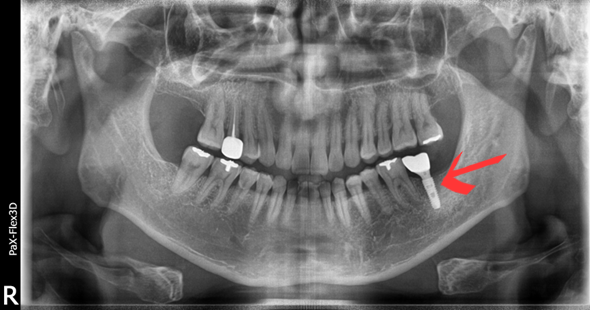

50대 남성분으로 본원에 오시기 2개월 전쯤 식사를 하시던 중 이가 깨지는 사고가 있었습니다.

곧바로 거주지 근처 치과에서 발치만 하시고, 임플란트 시술은 저희 디데이에서 진행하게 되셨는데요.

(전) 2021-09-29

사실 치아를 상실했을 때는 임플란트 시술을 빨리하는 것이 좋습니다.

치아가 없는 빈 공간으로 주변 치아가 옆으로 눕거나 이동하는 증상이 나타날 수 있기 때문입니다.

또한 위아래 치아가 서로 잘 맞물려야 하는데 이가 없다면, 남아있는 치아가 위로 올라가거나 아래로 내려앉는 증상이 생길 수 있어서 주의해야 합니다.

아울러 환자분은 치아가 없어 음식물이 계속 끼고, 말할 때 빈 공간이 보여 큰 불편감을 느끼셨는데요.